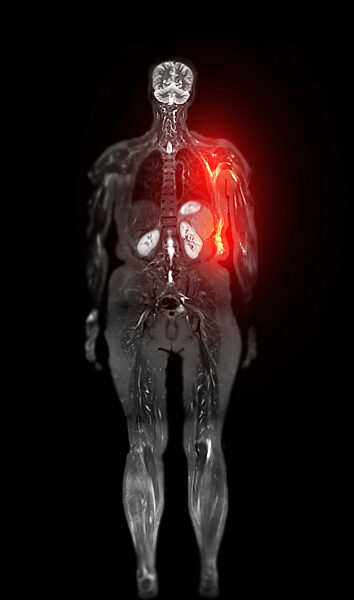

01.01.1000 - Coloured magnetic resonance imaging (MRI) whole-body scan showing recurrence of cancer in the left breast. Breast cancer is the most common cancer in women. It may appear initially...

560492033